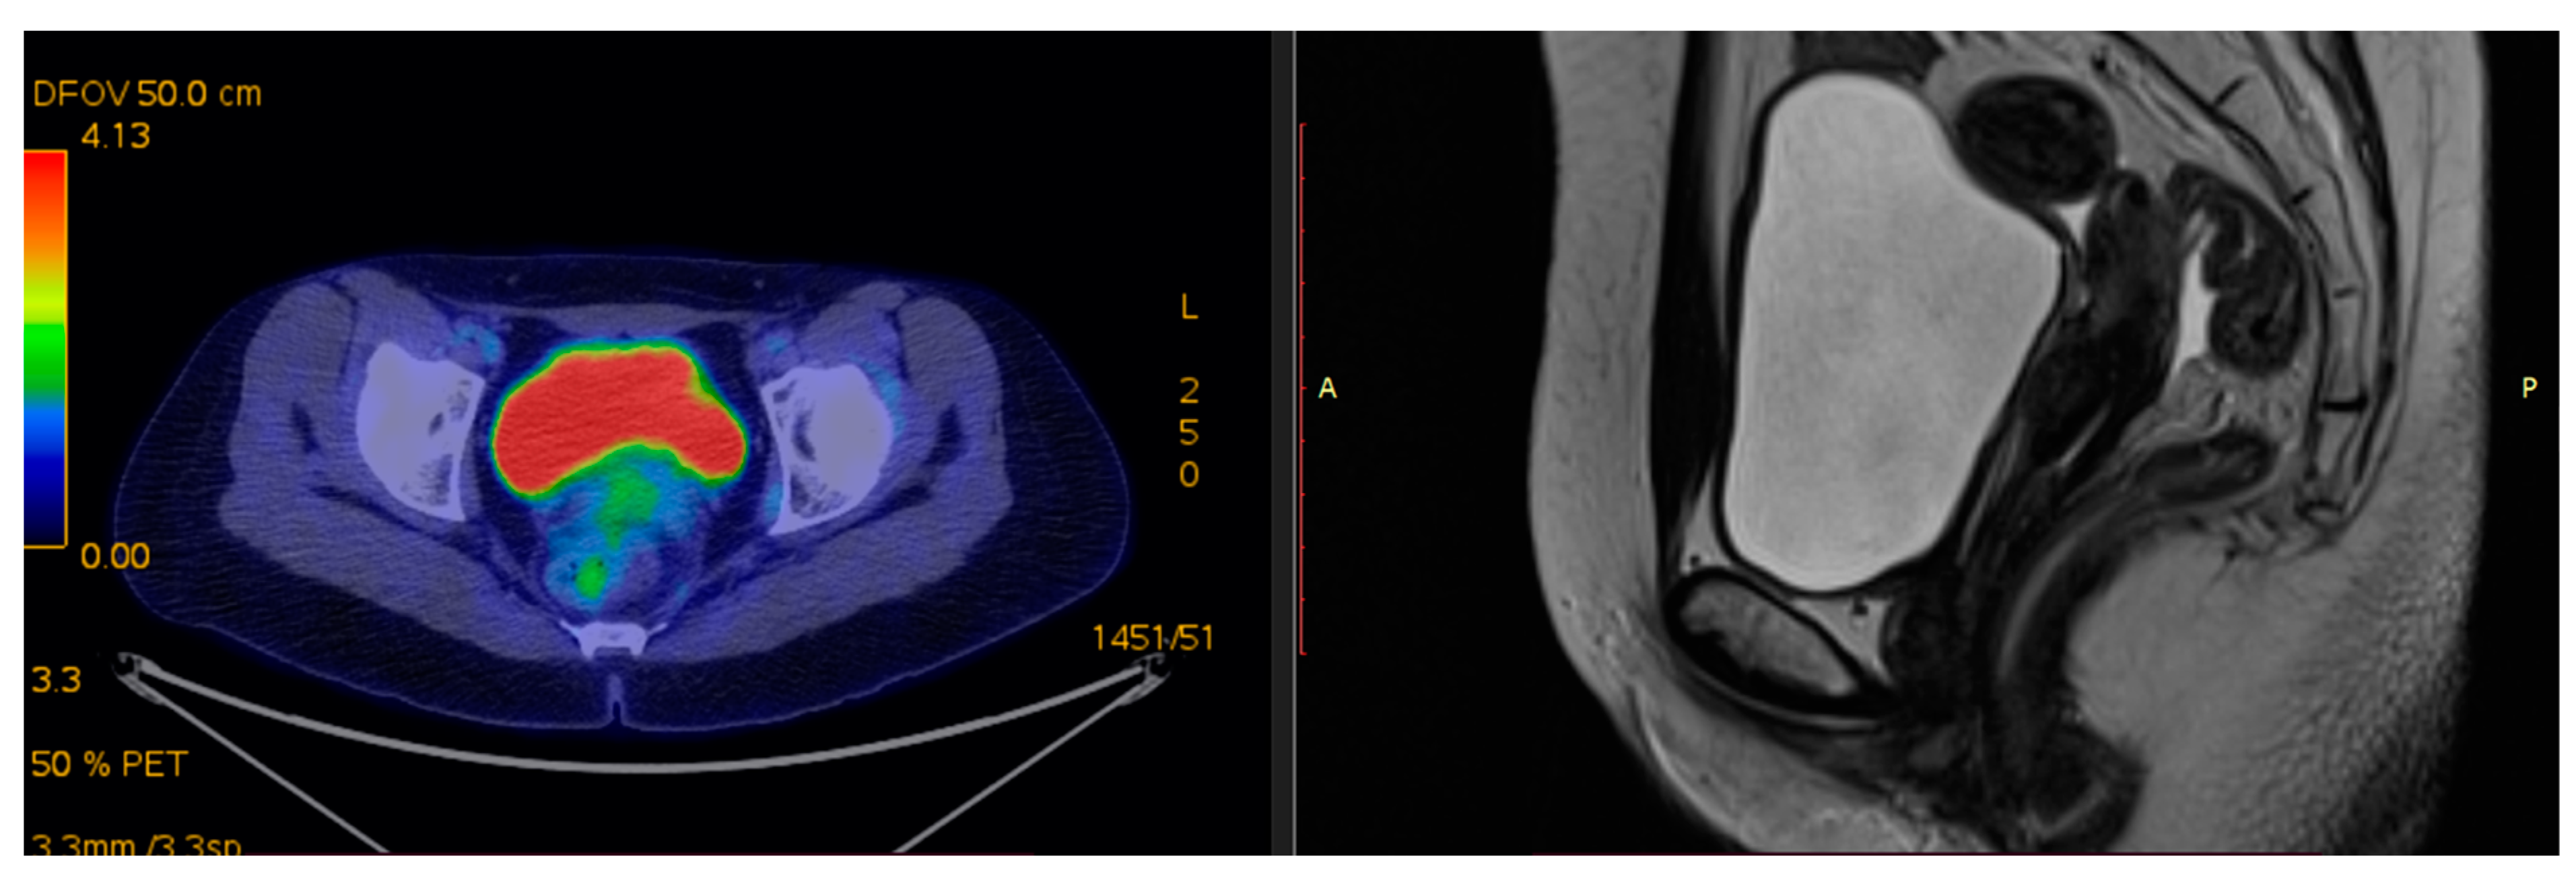

2.2. The Role of PET–CT

2.1. The Role of MRI